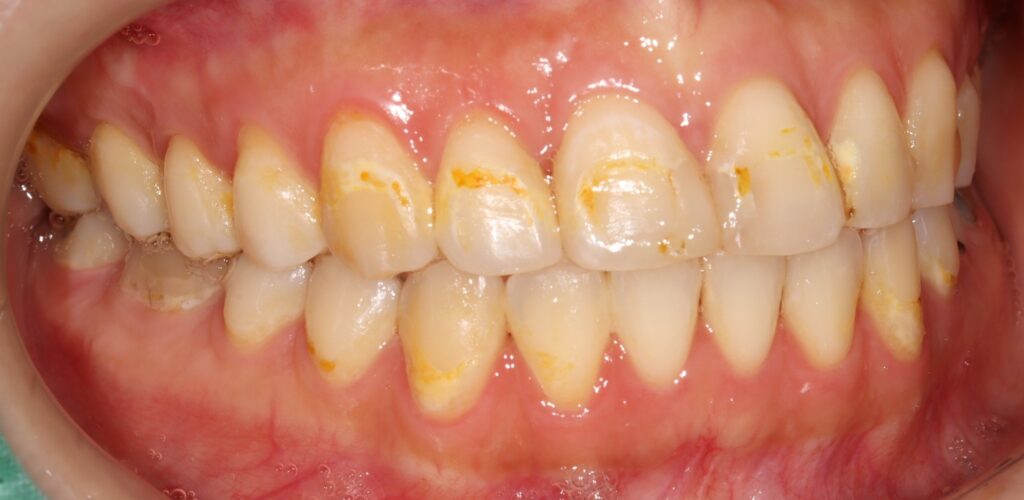

교정 장치 착용 기간 동안 구강 위생 관리가 어려워지면서

치아 표면에 착색이 생기거나,

치경부 부위에 우식이 발생하는 경우가

비교적 흔하게 나타납니다.

특히 전치부는 눈에 잘 띄는 부위이기 때문에

작은 변색이나 형태의 불균형만으로도

심미적인 불만으로 이어질 수 있습니다.

상악 전치부에는 눈에 띄는 착색과 함께

치경부 우식이 다수 관찰되었으며,

일부 치아에서는 구조적인 손상까지

동반된 상태였습니다.